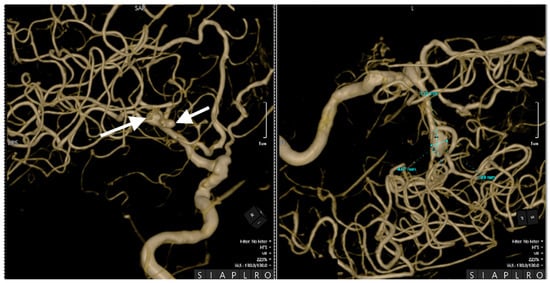

Cerebral angiography confirmed the presence of 2 ruptured saccular aneurysms at the bifurcation of the M1 segment of the right MCA (Figure 1, Figure 2 and Figure 3).

These rare vascular anomalies account for less than 1% of all intracranial aneurysms, making their diagnosis and management particularly challenging. Their anatomical proximity often results in misdiagnosis as a single, irregular, or lobulated aneurysm, increasing the risk of suboptimal treatment and delayed intervention [12,13,14]. In this case, advanced imaging techniques, particularly 3D digital subtraction angiography (3D-DSA), were pivotal in unraveling the precise configuration of the lesions. The high-resolution visualization provided by 3D-DSA allowed the identification of dual ruptures in the M1 segment of the MCA, facilitating a carefully tailored surgical strategy. Such precise imaging underscores the critical role of technology in transforming complex cases into manageable clinical scenarios [15,16].

Figure 2. Preoperative three-dimensional (3D) DSA rotational angiography. The 3D reconstruction of rotational DSA (left image) highlights the two kissing aneurysms (white arrows), one with 3 mm diameter and the other with a 7 mm diameter (right image).

Figure 3. Preoperative 3D DSA rotational angiography. In a high-resolution image, two kissing aneurysms are seen on the bifurcation of the M1 segment of the right MCA. The white arrows indicate the aneurysms' distinct locations, emphasizing their close proximity and shared arterial structures, which are characteristic of this rare vascular anomaly.